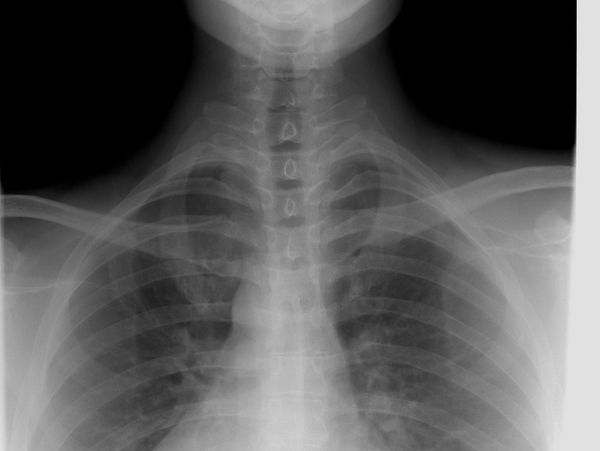

At Best Life Chiropractic, we believe that lasting health starts with a clear understanding of your spine and nervous system. That’s why we use state-of-the-art digital full-spine X-rays as part of our evaluation process. These images allow us to see the entire structure of your spine from top to bottom—not just one problem area—so we can provide the most precise and effective chiropractic adjustments possible.

Why Full-Spine X-Rays Matter

Many health problems don’t originate from just one spot in the spine. Issues in the neck can affect the shoulders, arms, and even lead to headaches, while problems in the lower back can influence the hips, knees, and feet. By viewing the entire spine under weight-bearing conditions, we can:

- Identify spinal subluxations (spinal misalignments) and postural imbalances

- Identify the Position and Condition of the Spine

- Detect disc problems, degeneration, or hidden injuries

- Understand how each part of the spine affects the body as a whole